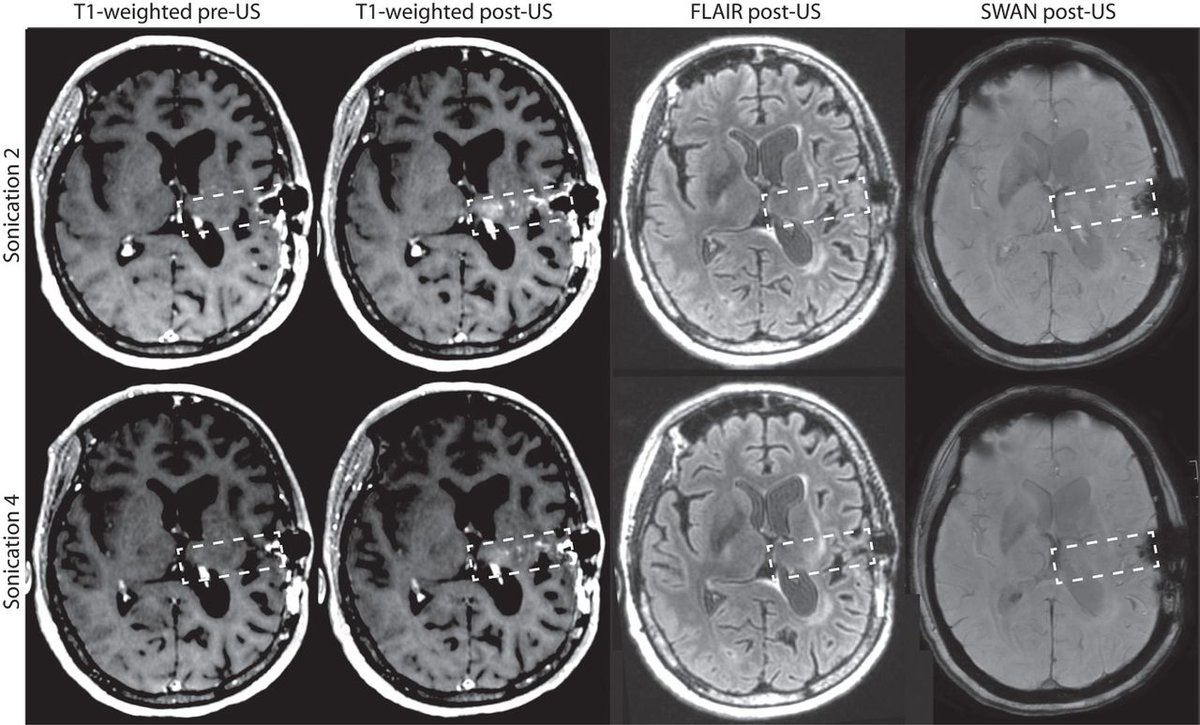

Ultrasound waves enhance drug delivery to the brain in cancer patients: http://scim.ag/1Uynmdm

#SciTMpic.twitter.com/Ce33JmFqOt